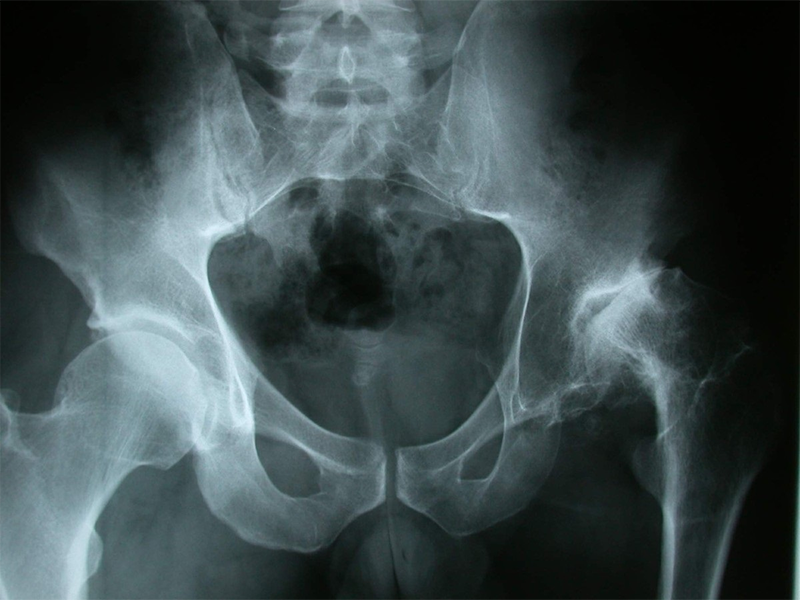

با پایبندی به این روشها و داشتن نگرش مثبت، میتوانید بر آرتروز خود کنترل بیشتری داشته باشید و از زندگی فعالتر و راحتتری لذت ببرید. به خاطر داشته باشید که درمان خانگی آرتروز لگن و بخشهای دیگر بدن یک سفر طولانیمدت است که نیازمند تعهد و صبر است.